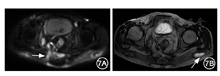

术后持续低压双套管冲洗引流10 d后拔出内套管,留置外管继续引流,口服全肠内营养(1 500 kcal/d,1 kcal=4.184 kJ)近1个月。患者体温正常,体重增长3 kg,白蛋白升高至35 g/L,营养状况明显改善,手术切口及皮肤瘘口恢复良好(图6)。术后1个月复查腹部磁共振(magnetic resonance,MR)提示:两侧后腹膜、盆壁、骶尾前区、双侧臀大肌仍有窦道及多发脓肿形成,但较术前明显好转(图7)。遂开始口服硫唑嘌呤25 mg/d,改全肠内营养为半肠内营养。

放射科:仔细阅读术前与术后1个月的影像学检查结果,可见患者术后虽然两侧后腹膜、盆壁、骶尾前区、双侧臀大肌仍有窦道与感染,但总体较术前好转。提示第一次外科手术疗效明确,而残余感染仍需进一步积极控制。